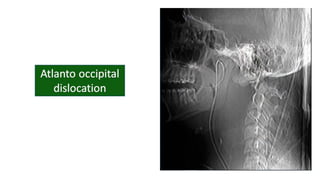

• Atlanto occipital dislocation

• #30 Sub- head is not properly aligned with the spine. Occipital cond to latermass relation ruined Distra- elevated increased distance bte occ cond and latermal masses

• #32 Occ cond floating And the whole cer spine is pushed backwardsin relation to the head

• #33 Basion dense interval <9.5mm

• #34 For true jeff Force hits the vertex of the head, go down through the occ condyles land on c1 and drive c1 to sides and disperse the fragments radially